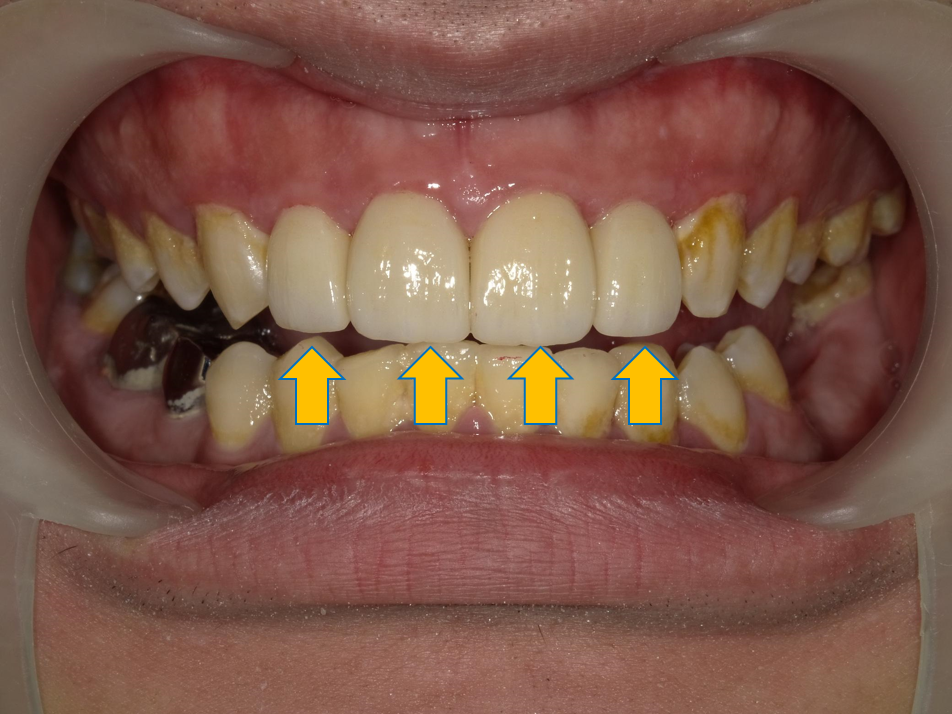

案例 2 術前(Before)

牙縫過大,舊有假牙不密合